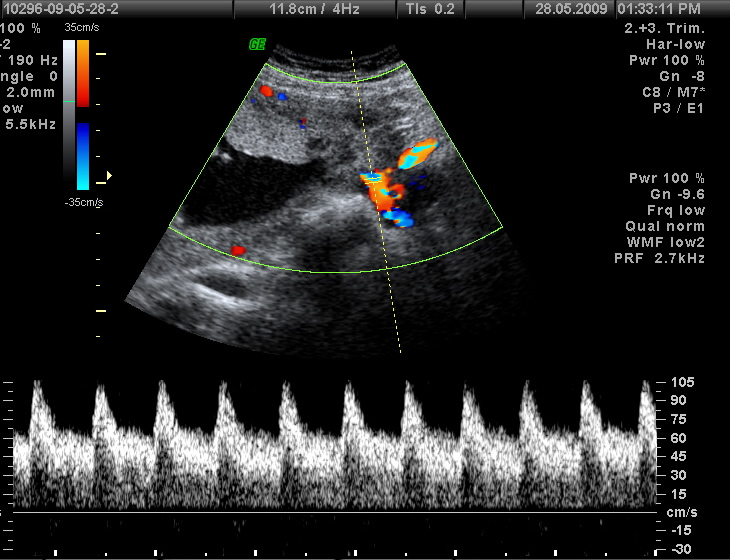

Que Es Un Ecocardiograma Doppler, 2 minutos por tu corazón: ¿Qué es un ecocardiograma doppler y para qué sirve, 2.61 MB, 01:54, 70,283, FundCardiologica, 2018-07-19T18:27:59.000000Z, 3, Ecocardiograma + Doppler Color - Cardiologo Tijuana - Cardiologia, cardiologiatijuana.com, 3453 x 2499, jpeg, WebEl Ecocardiograma Doppler es un examen no invasivo, que utiliza el ultrasonido para obtener las imágenes de las estructuras cardiacas y el efecto Doppler. WebUn ecocardiograma Doppler color es una variación de este examen cardíaco. Se utiliza una técnica especial para analizar mejor los movimientos del corazón, y se ha vuelto una., 20, que-es-un-ecocardiograma-doppler, Novedades y Muebles WebEl Ecocardiograma Doppler es un examen no invasivo, que utiliza el ultrasonido para obtener las imágenes de las estructuras cardiacas y el efecto Doppler. WebUn ecocardiograma Doppler color es una variación de este examen cardíaco. Se utiliza una técnica especial para analizar mejor los movimientos del corazón, y se ha vuelto una.

WebEl ecocardiograma doppler color o también llamado ecografía cardiaca es una prueba de la cardiología que nos permitirá valorar la estructura y función del corazón. Un.

WebDoppler de tejidos Ecocardiografía es un procedimiento médico que utiliza ultrasonido para examinar y medir las funciones del corazón. Se utiliza para determinar la velocidad y la. Web¿Qué es un ecocardiograma? El ecocardiograma es una prueba diagnóstica que se utiliza para visualizar de manera integral la estructura del músculo. WebUn ecocardiograma emplea ultrasonidos para reproducir imágenes del corazón. Esta prueba permite visualizar con gran exactitud la anatomía y fisiología del. WebEl eco Doppler es una técnica de ecografía que fue desarrollada a partir del efecto Doppler, que establece que la frecuencia de un sonido cambia cuando el objeto que lo produce. WebEl ecocardiograma es un examen ambulatorio. Esto quiere decir cuando su ecocardiografía termine, se podrá retirar a su casa, a no ser que el paciente tenga algún. WebLa ecografía Doppler es una prueba no invasiva que calcula el flujo de la sangre en los vasos sanguíneos haciendo rebotar ondas sonoras de alta. WebUn ecocardiograma usa ondas sonoras para producir imágenes del corazón. Esta prueba común le permite al médico ver cómo el corazón late y bombea. WebUn ecosonograma o ecografía es una prueba de diagnóstico médico por imagen que utiliza ondas sonoras. Por lo tanto, se trata de una técnica sin riesgo que no.

WebUna ecografía Doppler cardíaca, también conocida como ecocardiograma Doppler, es una prueba médica que sirve para observar el corazón en movimiento con. WebEcocardiograma Doppler. Cuando se trata de realizar un Ecocardiograma Doppler puedes tener la seguridad de que no es un procedimiento invasivo y no requiere preparación. WebEl ecodoppler cardíaco en reposo (o ecocardiograma) es una prueba a través de la cual el médico puede visualizar el corazón en una computadora especial,.